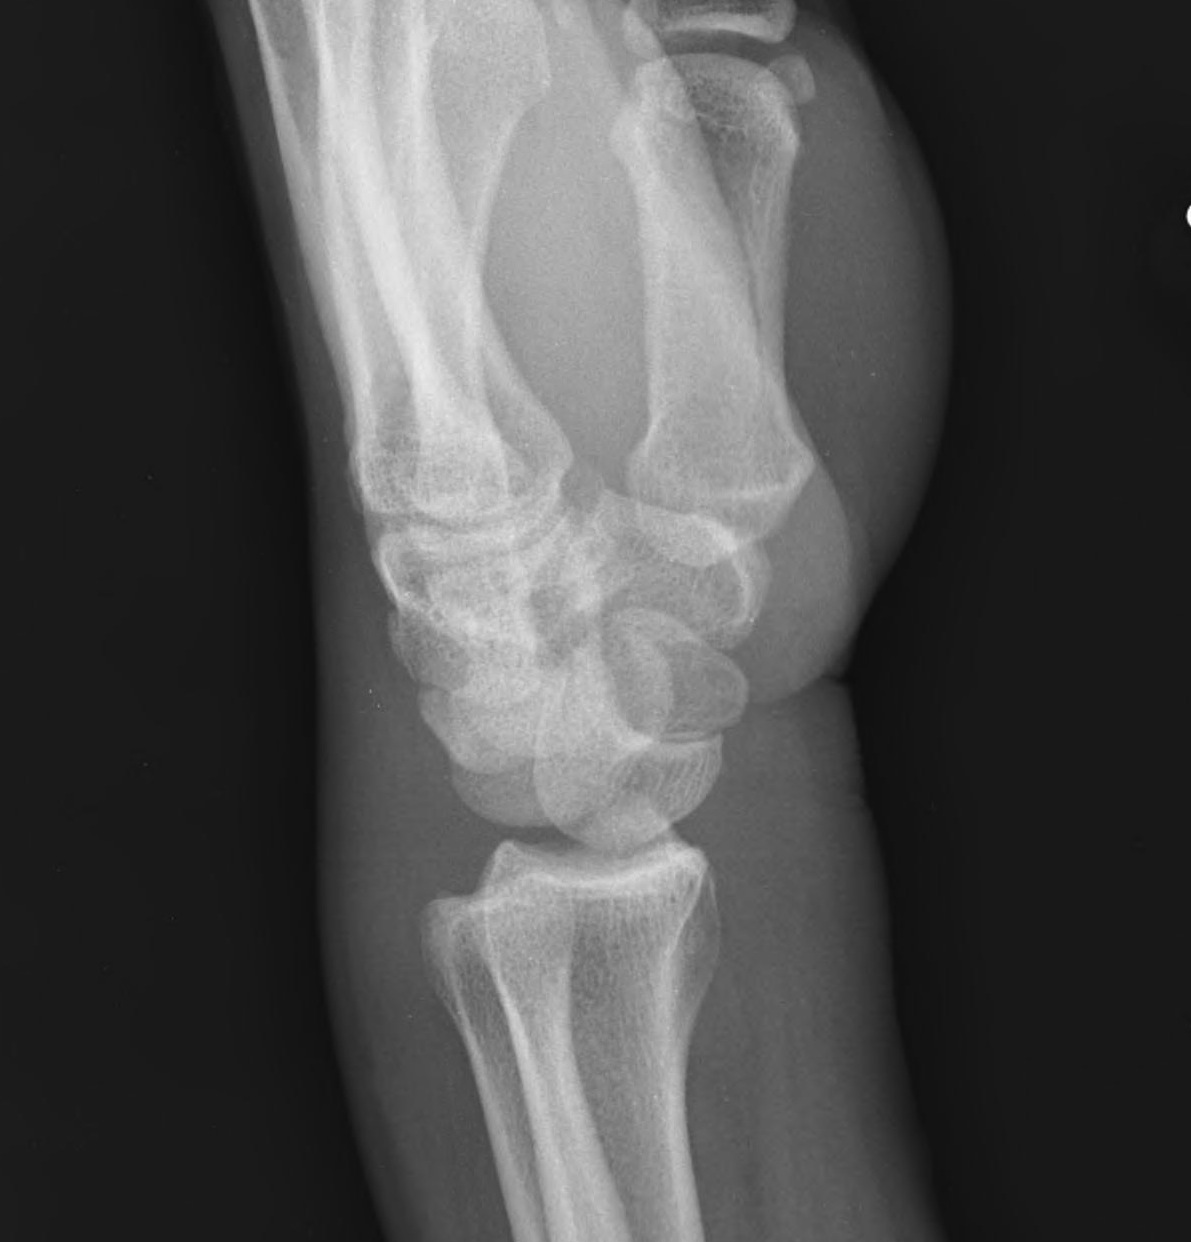

X-ray

Disruption of Gilula's 3 smooth carpal arcs

Progressive Injury

1. Capitate dorsal

- lunate remains with radius

- lunate looks triangular on AP

2. Lunate dislocates

- usually volar